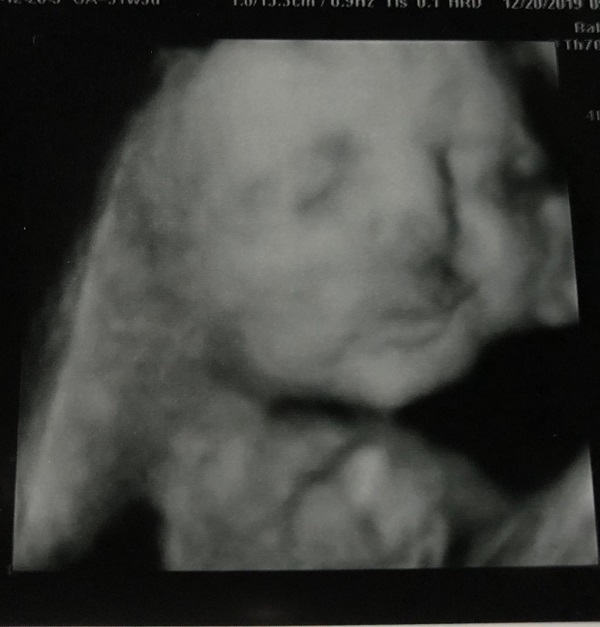

The tech could go from the regular ultrasound to the 3D pictures, and it was very cool to see. We will be going back later in the pregnancy to see more. They told us that at this young, it is a bit hard to see and that there were things that were still developing. This is a shot of our baby with her hand up near her face. It was very cool to see and I am excited to see her again in a few months.